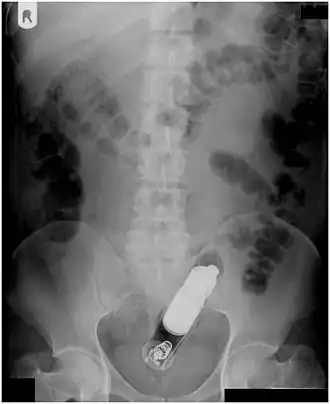

| Radiograph of a male abdomen with a vibrator inside the rectum | |

Rectal foreign bodies are large foreign items found in the rectum that can be assumed to have been inserted through the anus, rather than reaching the rectum via the mouth and gastrointestinal tract. It can be of clinical relevance if the patient cannot remove it the way they intended. Smaller, ingested foreign bodies, such as bones eaten with food, can sometimes be found stuck in the rectum upon X-ray and are rarely of clinical relevance.

Usually, several radiological images are recorded in order to pinpoint the precise place and depth of the foreign body. This is usually done by X-ray. Foreign bodies made from low-contrast material (e.g. plastics) may necessitate medical ultrasound or a CT scan.[29] Magnetic resonance imaging is contraindicated, especially if the foreign body is unknown. Foreign rectal bodies may penetrate deep into the colon, in certain circumstances up to the right colic flexure.[10]